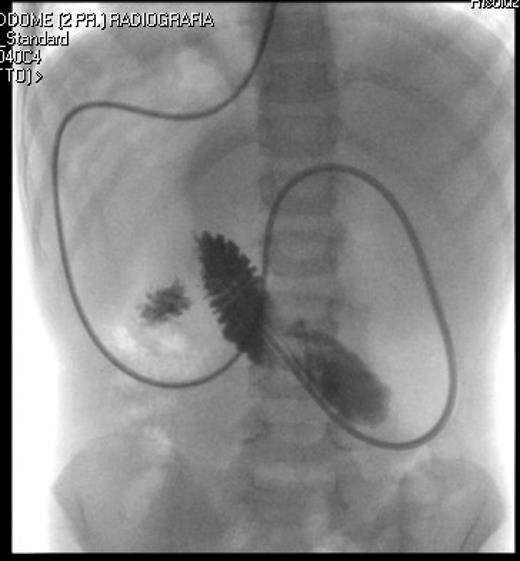

A 7-year-old boy who had been treated at 3 years of age for a subtotal colonic Hirschsprung disease with a Deloyers’ procedure was admitted for persistent bilious vomit associated with recurrent episodes of postprandial abdominal pain and diarrhea. The parents reported a progressive weight loss of 3.5 kg during the last 3 years. The patient was emaciated with severe chronic malnutrition; the weight and the length were 15.19 kg and 113 cm [body mass index (BMI): 11.9 kg/m2], both between the third and the fifth percentile, respectively. The clinical abdominal examination was normal. A plain abdominal X-ray showed a distended stomach with paucity of gas in the distal bowel. An abdominal ultrasound confirmed a dilated duodenum without signs of mechanical obstruction of the small bowel and a normal relationship between the superior mesenteric vessels. An upper gastrointestinal contrast study confirmed dilatation of the first and second portions of the duodenum with little progression of contrast medium across the third portion released in left lateral position (Fig. 1). An SMAS was confirmed by a computed tomography (CT) scan that showed a reduction in retroperitoneal preduodenal and mesenteric fat and compression of the third duodenum by the superior mesenteric artery with an acute 13° angle and a 7.5 mm distance from the aorta (Fig. 2). A gastrointestinal endoscopy confirmed the dilatation of the duodenum with an inflammatory mucosa and a normal jejunum. Gastric and duodenal biopsies were performed and a nasojejunal tube was guided through the duodenum to the Treitz to start enteral feeding (Fig. 3).

The upper gastrointestinal contrast study shows poor progression of contrast medium across duodenal obstruction. Arrow shows obstruction of the third duodenum.